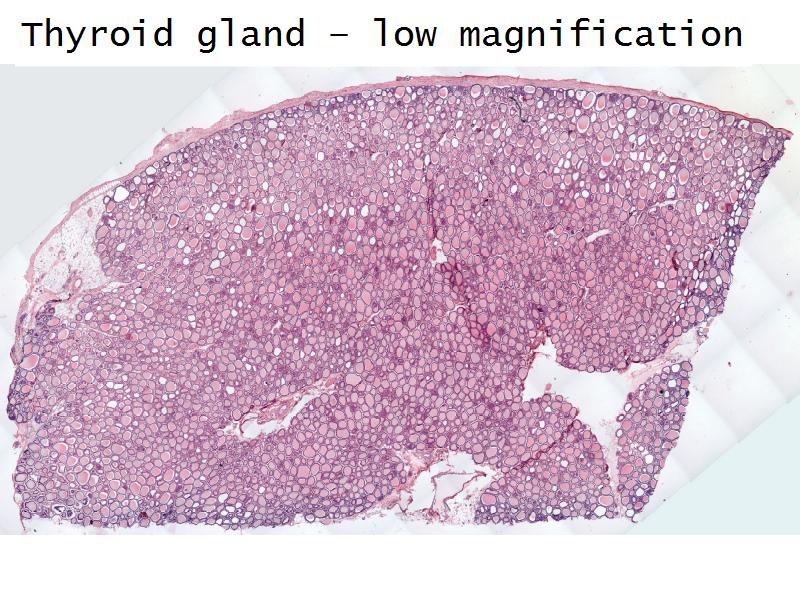

Thyroid gland

Four elements making up the thyroid

Thyroid gland

- Follicle